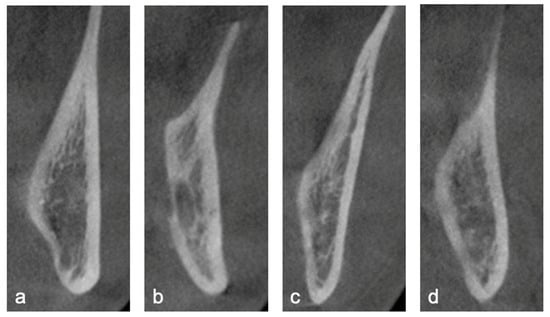

- Lingual Plate Morphology: Morphology of the lingual cortical bone at the level of the root apex was classified as undercut, parallel, slanted, or round (Figure 1).